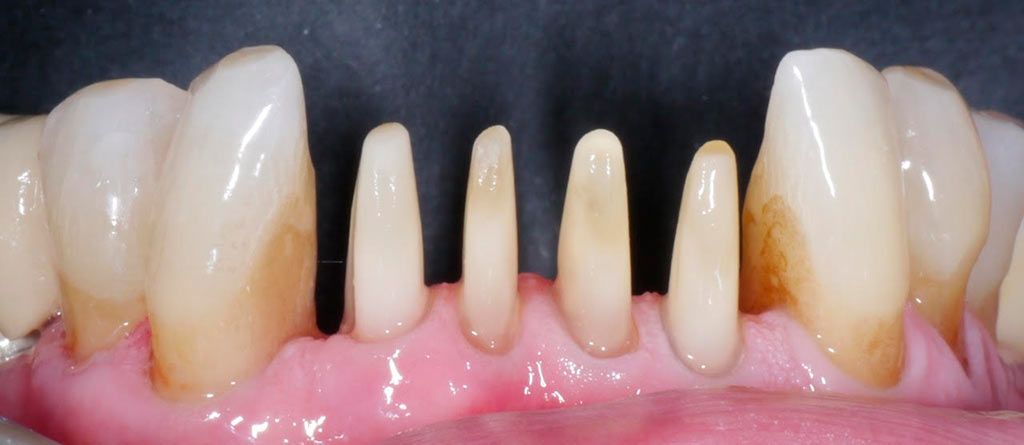

Rehabilitacion de paciente con destrucción dental